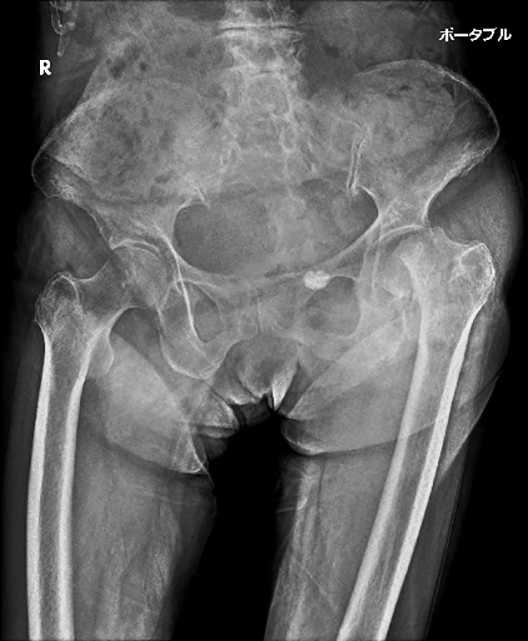

2例目は、85歳の女性で、基礎疾患として腰部脊柱管狭窄症と過活動膀胱がある施設入所中の方です。ADLは歩行器歩行で、日曜日に転倒されて左足の痛みを訴えられていました。1例目と同様に、診察の所見で十分に骨折が疑われましたが、X線撮影を行うと、やはり左の大腿骨の転子間骨折が認められました。(写真3)

佐賀市の我々の地域では、日曜日にこうした症例に対応できる病院が限られており、時間帯によっても搬送先を変える必要があるため、しっかりと骨折を確認して適切な病院に搬送しました。